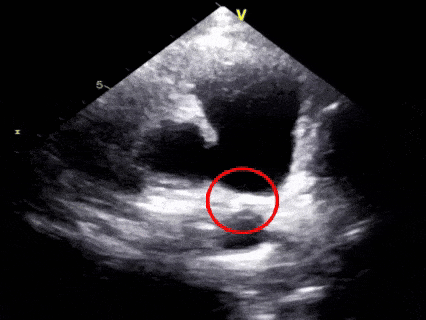

二“扣”,双盘扣合

超声下可见右盘面展开后盘面骑跨在肺动脉与主动脉两侧

三“锁”,成型锁定

多切面确认封堵器形态良好,一侧在肺动脉一侧在主动脉

胸骨旁主动脉短轴切面

胸骨上窝主动脉弓长轴切面